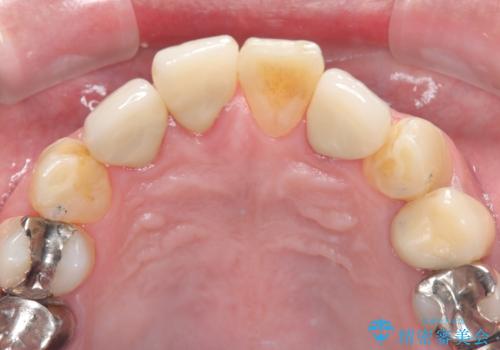

古い被せ物を除去しオールセラミッククラウンで治療を行いました。

- 495,000円(オールセラミッククラウンスペシャル154,000円×3本+仮歯11,000円×3本)費用は治療当時の料金となります

被せ物の適合が悪く劣化もおこし色が変色している状態でした。そのため他の歯とも色が合っていませんでした。古い被せ物を除去し形を整えた後にオールセラミッククラウンで治療を行いました。